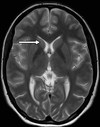

A

quadrigeminal cistern